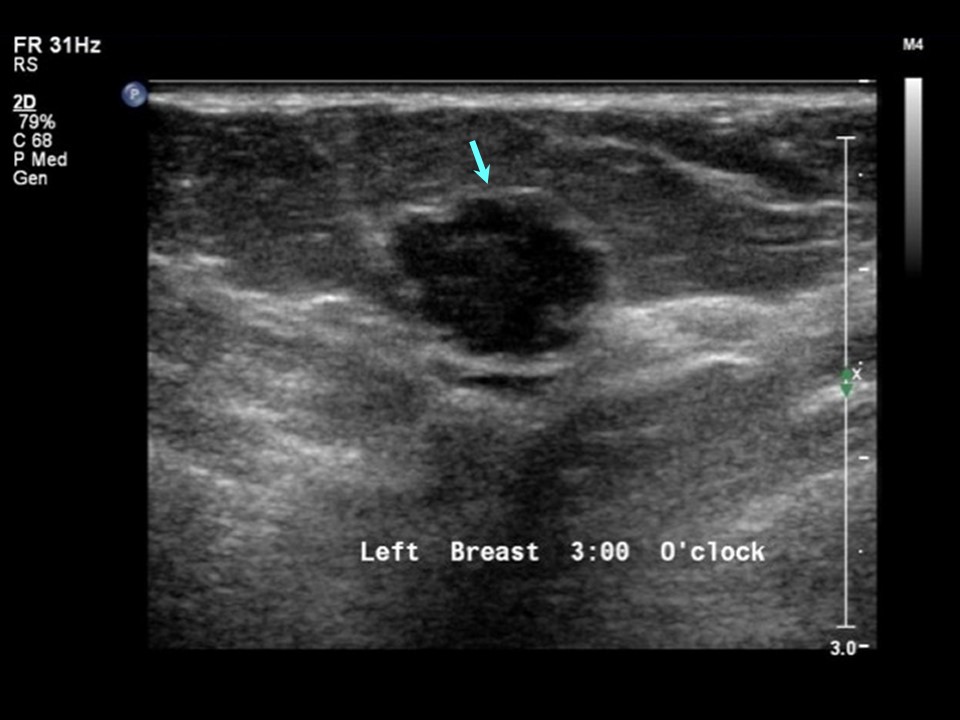

From www.msdmanuals.com

Image Ultrasound of a Breast Lump MSD Manual Professional Edition Painful Breast Lump Ultrasound To diagnose a breast cyst, your women’s health provider will discuss your symptoms and health history and perform a. A painful lump in the breast is not usually a sign of breast cancer. The mammogram itself was uncomfortable, but not painful. While cysts are typically not cancerous, a solid lump may. Pain in one or both breasts can be caused. Painful Breast Lump Ultrasound.